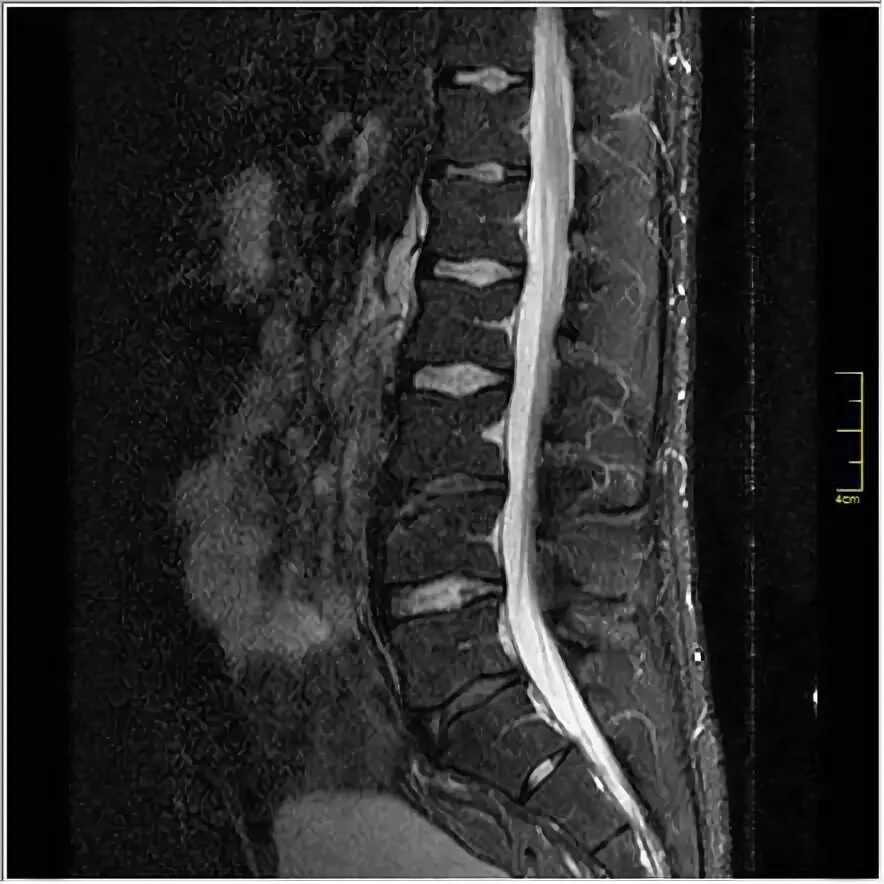

Limbus 3